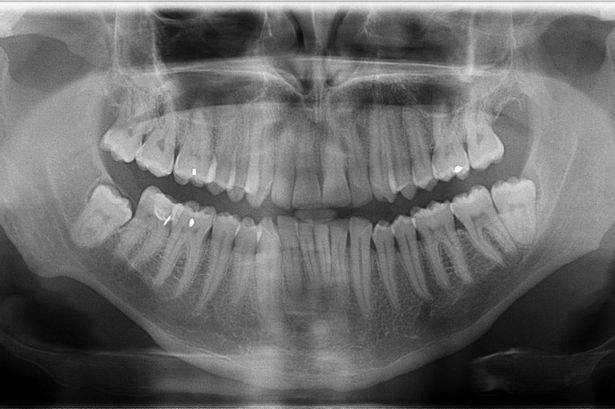

As mentioned above, it is hard (any potentially undesirable) to directly build a GDP from biomedical images. We hence learned the prior from natural-scene images, but validate it here on biomedical images. We first show stability of the present GDP for biomedical images. For this, we collected a small dataset of biomedical images, including X-ray, MRI, electron microscopy, and fluorescence microscopy images. Some examples are shown in Figs. 10 and 24.